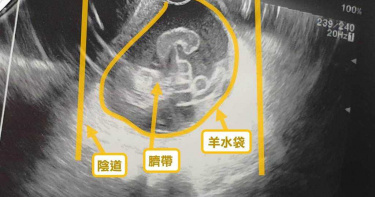

懷孕31周劇烈宮縮 檢查驚見「臍帶脫垂」險胎死腹中

花蓮一名37歲陳姓女子相隔13年再迎第二胎,31周在門諾醫院住院安胎時,因持續子宮早期收縮,檢查竟發現,陰道內有約7公分羊水袋,且充滿臍帶,是罕見「臍帶脫垂」,恐阻斷供血胎兒,緊急剖腹後,順利保住母女;醫師提醒,孕婦若有早期子宮持續收縮等狀況,要留意是否為臍帶脫垂,如果不跟時間搶快,可能造成胎兒缺氧、早產、胎死腹中,產婦也可能因大出血而休克甚至死亡。臍帶脫垂發生率僅有0.1%至0.3%,雖然不常見,但對胎兒危害極大!門諾醫院婦產科醫師吳文綺強調,胎兒藉臍帶從母體吸收營養與氧氣,一旦臍帶掉落在子宮頸口或陰道內,就會造成臍帶血液循環受阻,且超過3分鐘就可能導致胎兒缺氧。吳文綺說,若無法及時處理,對胎兒腦部會造成永久傷害,嚴重則可能會窒息死亡;臨床上,很少有醫師會去用陰道超音波檢查羊水袋,通常都是等破水後,寶寶心跳下降,窘迫時,才發現臍帶脫垂, 但搶救時間就會有些延遲,因此造成結果大不同。陳女看著熟睡的女兒說,原以為可自然產,沒想到卻在29週後出現出血情形,經歷2次住院安胎後,31週感到劇烈宮縮,經醫師檢查除了有早產現象,還發現臍帶掉到陰道,是少見危險的「臍帶脫垂」,所幸醫護團隊努力,女兒出生時只有1748公克,經3周住院治療,體重突破2300公克,陳女和丈夫鬆了一口氣「終於可以回家」。吳文綺提醒,若孕婦有子宮早期收縮的早產現象,或足月卻發生高位破水等,都有可能造成產前臍帶脫垂的危險,因此,羊水問題也不能輕忽,最重要的是做好每一次的產前檢查,避免產婦及胎兒陷入危險。